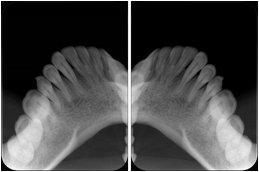

1. A patient in rural Canada visits a general ophthalmologist and is found to have diabetic macular edema. The general ophthalmologist would like to discuss the case with a retina specialist before performing laser surgery. A fluorescein angiogram is done with multiple retinal images taken in a timed series after an intravenous injection. The images along with a Structured Display are shared via a Health Information Exchange with a retina specialist in Calgary, who opens them using his Ophthalmology EMR software and consults via phone with the general ophthalmologist. Both physicians view the images in the same layout so the retina specialist can provide accurate guidance for treating the patient.

2. A patient in rural Iowa visits his primary care physician for management of diabetes. Three non-mydriatic (patient's eyes are not dilated) photographs are taken of the back of each eye, and forwarded electronically along with a Structured Display to an ophthalmologist in Iowa City. The ophthalmologist reads the photos in an agreed upon layout so there is no mistake about what portion of which eye is being viewed. The ophthalmologist is able to tell the primary care physician that his patient does not need to come to Iowa City for face to face ophthalmologic care, but that there is a particular view of the left eye that should be photographed again in 6 months.

Ophthalmic Retinal Study Structured Display

Figure OO-3. Ophthalmic Retinal Study Structured Display